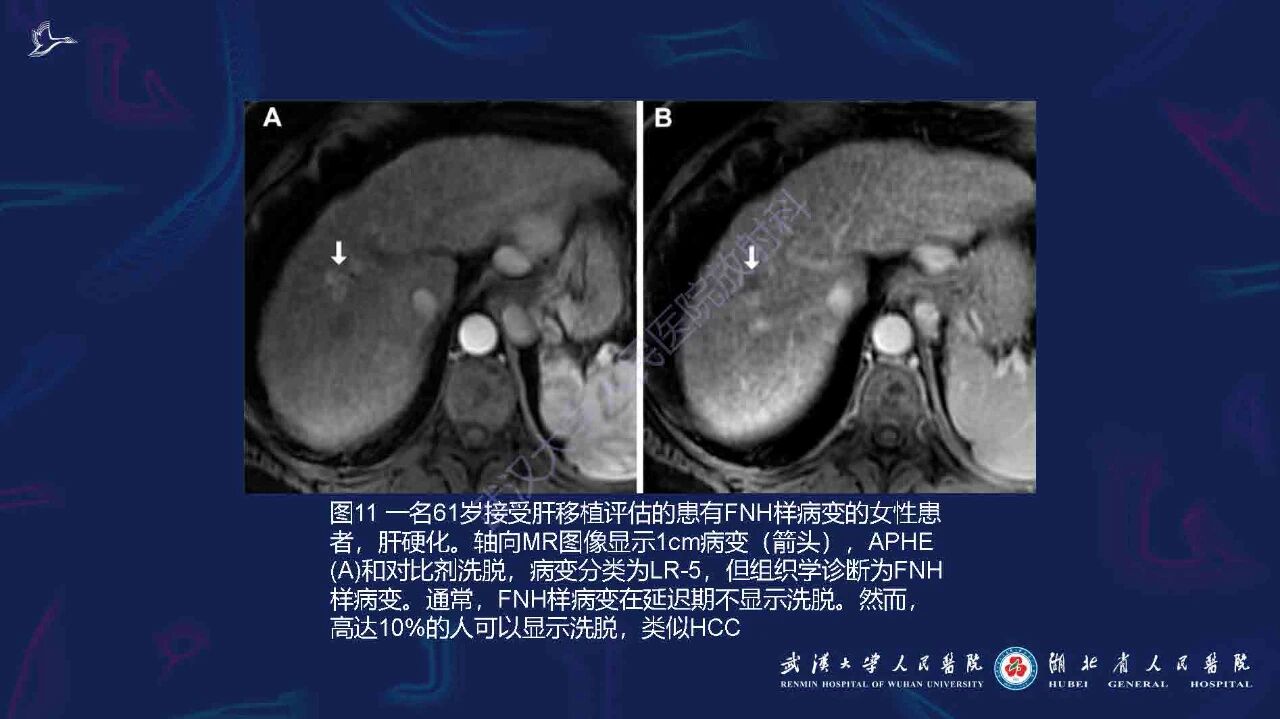

肝硬化伴肝内局灶性病变影像诊断